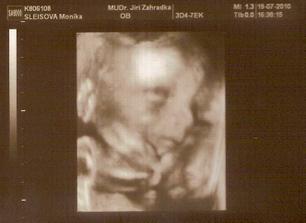

10.5. druhá poradna, prý je dlouho vše v pořádku a tak výsledky z krve říkají, že máme zvýšené riziko na trisomii 21 (Down) - 1:55

11.5. NT screening, jsem 13+5 a teď čekáme.....12.5. výsledky jsou v normě! 🙂